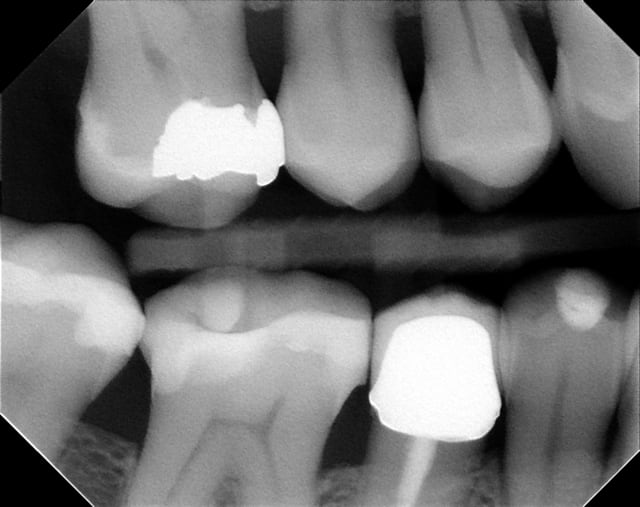

oui, Noah,voici les radiographies de ce patient

j'ai fait un p'tit détour au cab.

merci

flicfac, en ce qui concerne la 46, tu as d'après ton bilan de sondage une atteinte de furcation de grade III, ce qui signifie que ton potentiel de régénération est nul.

réevaluation finale avant d'adresser la patiente en ortho.